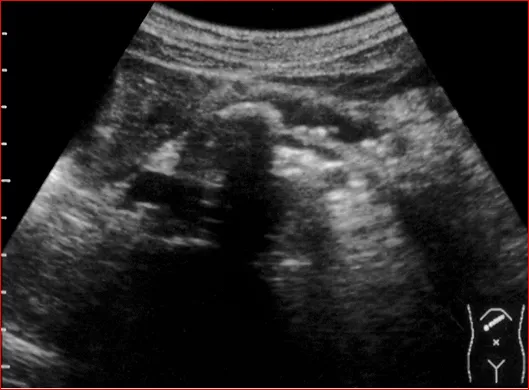

饮水后上腹部横切,显示胰尾部占位与胃体后壁的关系